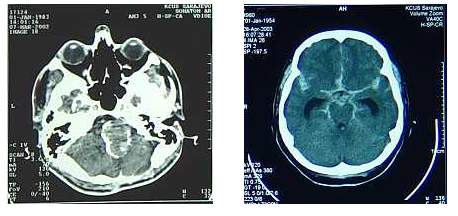

Tako npr. kod hemoragične CV bolesti, CT odmah pokazuje hiperdenzitet

u moždanom parenhimu (ako se radi o intracerebralnom hematomu), dok kod

SAH (subarahnoidalnih hemoragija) ta pouzdanost je manja, a 20% sigurnih

SAH se ne vidi CT skenom. S druge strane, nema SAH koja ima bistar, bezbojan

likvor.

Dijagnostika

Kod ishemične CV bolesti, CT ne pokazuje odmah promene,

treba da prođe od par sati do 48 sati, zavisno od veličine insulta, a

nakon 8 dana se vide definitivne granice moždanog infarkta.